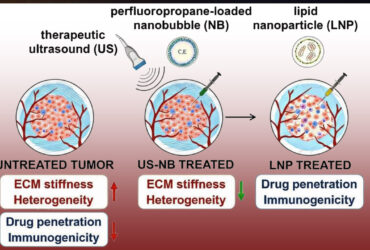

فناوری نانوحباب، تنها به حوزهی تصفیه محدود نمیشود؛ بلکه در بخشهایی چون آبیاری هوشمند کشاورزی، پرورش آبزیان، صنایع نیمههادی، بازیابی نفت، نگهداری مواد غذایی و حتی پزشکی، جایگاه روبهرشدی یافته است.

از سوی دیگر، کاربردهای متنوع این فناوری در آبزیپروری، کشاورزی، نیمههادی، نفت و گاز، صنایع غذایی و پزشکی، ظرفیتهای گستردهای برای سرمایهگذاری به وجود آورده است.